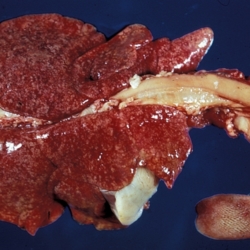

Pàgina anterior de 637 Pàgina següent 3181 total Bovine Specie: Bovine Organ: Trachea Lesion: Tracheitis Lesion modifier: Tracheitis - Granulomatous Disease: Tuberculosis Position: 253 (1 views) Ovine Specie: Ovine Organ: Lung Lesion: Pneumonia Lesion modifier: Pneumonia - Granulomatous Disease: Tuberculosis Position: 59 (4 views) Feline Specie: Feline Organ: Lung Lesion: Pneumonia Lesion modifier: Pneumonia - Granulomatous Disease: Tuberculosis Not viewed Feline Specie: Feline Organ: Lung Lesion: Pneumonia Lesion modifier: Pneumonia - Granulomatous Disease: Tuberculosis Not viewed Canine Specie: Canine Organ: Lung Lesion: Carcinoma Lesion modifier: Carcinoma - Adenocarcinoma Disease: - Files/Expedient: N-103/15 Position: 253 (1 views) Pàgina anterior de 637 Pàgina següent Títol Select...Avian (Exotic) (110)Avian (Poultry) (76)Bovine (317)Canine (935)Caprine (47)Equine (257)Feline (326)Ferret (19)General (127)Marine mammal (22)Non-human primate (20)Ovine (328)Porcine (379)Rabbit (61)Reptile (38)Rodent (28)Wildlife (91) Format Select...- (60)Abomasum (37)Adrenal gland (10)Blood (7)Blood vessel (50)Body as a whole (19)Bone (57)Bone marrow (21)Brain (93)Cloaca (1)Diaphragm (2)Ear (5)Esophagus (39)Eye (16)Fetus (12)Gallbladder (23)Gizzard (2)Heart (265)Intestine (356)Joint (32)Kidney (443)Larynx (5)Liver (326)Lung (264)Lymph node (91)Mammary gland (10)Mediastinum (1)Muscle (22)Nasal cavity (22)Nerve (7)Omasum (5)Oral cavity (63)Ovary (14)Oviduct (8)Pancreas (7)Parathyroid (5)Penis (10)Peritoneum (65)Pharynx (9)Pituitary gland (6)Placenta (7)Prostate (8)Proventriculus (3)Reticulum (1)Rumen (28)Sinus (7)Skin (181)Spinal cord (15)Spleen (105)Stomach (125)Teeth (1)Testicle (11)Thoracic cavity (31)Thymus (13)Thyroid gland (5)Tongue (32)Tonsils (11)Trachea (11)Urethra (5)Urinay bladder (61)Uterus (27)Vagina (1)Vulva (1)Yolk sac (1) Cobertura Select...- (152)Abomasitis (26)Abscess (27)Acidosis (1)Adenocarcinoma (20)Adenoma (9)Aerosacculitis (6)Agenesis (1)Agnathia (1)Alopecia (7)Amyloidosis (12)Aneurysm (6)Angiectasis (1)Anthracosis (1)Arteritis (11)Arthritis (15)Arthrogryposis (6)Artifact (4)Ascites (13)Atelectasis (8)Atherosclerosis (5)Atresia (1)Atrial septal defect (2)Atrophy (10)Autolysis (7)Bronchitis (6)Bronchopneumonia (26)Cachexia (2)Carcinoma (103)Cardiomyopathy (19)Cellulitis (2)Chemodectoma (4)Cholangiohepatitis (4)Cholangitis (19)Cholecystitis (4)Cholestasis (5)Chondrodysplasia (2)Chondrosarcoma (2)Chronic passive congestion (13)Chylothorax (2)Cirrhosis (6)Coelomitis (3)Coenurus cerebralis (4)Colitis (40)Congestion (17)Conjunctivitis (5)Coronitis (3)Cryptorchidism (3)Cyst (25)Cystitis (24)Dermatitis (69)Diaphragmatic hernia (4)Dilation (28)Discospondylitis (1)Disseminated intravascular coagulation (7)Dyschondroplasia (1)Dysplasia (29)Ectopia cordis (1)Ectopic ureter (1)Edema (55)Emphysema (5)Encephalitis (5)Endocardiosis (14)Endocarditis (26)Endometritis (5)Enteritis (118)Enterolith (6)Epulis (3)Esophagitis (14)Fasciitis (1)Fibrosis (7)Fibrous osteodystrophy (8)Fistula (1)Folliculitis (3)Fracture (2)Gastritis (34)Gingivitis (5)Glioma (8)Glomerulonephritis (21)Glossitis (25)Glycogenosis (1)Gout (8)Granuloma (2)Granulosa cell tumor (4)Hemangioma (9)Hemangiosarcoma (46)Hematoma (8)Hemoglobinuria (2)Hemopericardium (12)Hemoperitoneum (2)Hemorrhage (100)Hemosiderosis (7)Hemothorax (2)Hepatitis (78)Hernia (11)Histiocytosis (3)Hydatid cyst (11)Hydrocephalus (9)Hydrometra (1)Hydronephrosis (22)Hydropericardium (6)Hydrothorax (3)Hydroureter (5)Hyperkeratosis (8)Hyperostosis (4)Hyperplasia (37)Hypertrophy (9)Hypopigmentation (1)Hypoplasia (7)Hypopyon (1)Impaction (6)Infarction (63)Insulinoma (6)Intussusception (5)Jaundice (17)Laminitis (2)Laryngitis (2)Leiomyoma (5)Leukemia (13)Lipidosis (36)Lipoma (7)Lymphadenitis (45)Lymphadenopathy (7)Lymphangiectasia (6)Lymphangitis (5)Lymphoma (221)Malacia (11)Malignant melanoma (15)Mast cell tumor (11)Mastitis (8)Megaesophagus (2)Melanosis (3)Melena (4)Meningioma (6)Meningitis (6)Meningocele (2)Meningoencephalitis (5)Mesothelioma (5)Methemoglobinemia (2)Mineralization (10)Mucocele (5)Mucometra (1)Multilobular bone tumor (1)Mummification (3)Myelofibrosis (1)Myocarditis (4)Myositis (5)Necrosis (81)Nephritis (113)Nephroblastoma (6)Nephrosclerosis (1)Nephrosis (14)Neuritis (1)Obstruction (13)Omasitis (4)Omphalitis (1)Omphalophlebitis (7)Orchitis (4)Osteoarthrosis (5)Osteomyelitis (9)Otitis (2)Palatoschisis (3)Pancreatitis (3)Panniculitis (3)Papilloma (7)Parakeratosis (14)Patent ductus arteriosus (6)Peliosis hepatis (1)Perforation (17)Pericarditis (35)Peritonitis (39)Persistent right aortic arch (1)Pharyngitis (2)Pheochromocytoma (2)Phlebitis (2)Placentitis (6)Pleuritis (21)Pleuropneumonia (24)Pneumonia (109)Pneumothorax (3)Polycystosis (14)Polyp (5)Polyserositis (6)Posthitis (1)Proctitis (4)Prolapse (3)Prostatitis (3)Proventriculitis (1)Pyelonephritis (24)Pyometra (6)Pyothorax (4)Rhinitis (11)Rumenitis (6)Rupture (24)Salpingitis (3)Sarcoma (57)Sclerosis (1)Scoliosis (2)Seminoma (2)Sequestrum (2)Serous atrophy (14)Sinusitis (7)Splenitis (14)Splenomegaly (9)Spondylitis (6)Spondylosis (1)Stenosis (9)Stomatitis (32)Tenosynovitis (2)Teratoma (3)Thricobezoar (2)Thrombosis (16)Tonsilitis (4)Torsion (13)Tracheitis (4)Tympany (7)Typhlitis (8)Typhlocolitis (4)Ulcer (43)Urethritis (1)Urolithiasis (36)Uroperitoneum (1)Uveitis (1)Vasculitis (15)Ventricular septal defect (3)Volvulus (11) Matèria Select... - (14)- (1653)- (152)Abomasitis - Catarrhal (2)Abomasitis - Catarrhal-hemorrhagic (1)Abomasitis - Chronic (1)Abomasitis - Fibrinous-necrotizing (2)Abomasitis - Hyperplasic (5)Abomasitis - Hyperplasic - Chronic (1)Abomasitis - Necrotic (1)Abomasitis - Necrotizing (2)Abomasitis - Ulcerative (5)Adenocarcinoma (9)Aerosacculitis - Granulomatous (1)Amyloidosis - Chronic (1)Arteritis - Necrotic (2)Arteritis - Necrotizing (1)Arthritis - Chronic (4)Arthritis - Fibrinous-purulent (3)Arthritis - Serous (4)Arthritis - Subacute (1)Ascites - Serous (1)Atrophy - Serous (1)Bronchitis - Catarrhal (3)Bronchitis - Suppurative (1)Bronchopneumonia - Catarrhal-purulent (17)Bronchopneumonia - Fibrinous (1)Bronchopneumonia - Granulomatous (1)Bronchopneumonia - Purulent (1)Bronchopneumonia - Suppurative (5)Carcinoma - Adenocarcinoma (33)Carcinoma - Adenocarcinoma - Hepatocellular (2)Carcinoma - Adenocarcinoma - Mucinous (1)Carcinoma - Basosquamous (1)Carcinoma - Cholangiocellular (3)Carcinoma - Hepatocellular (4)Carcinoma - Metastatic (3)Carcinoma - Squamous cell carcinoma (13)Carcinoma - Transitional cell (2)Cardiomyopathy - Dilated (13)Cardiomyopathy - Hypertrophic (6)Cellulitis - Necrotizing (1)Cholangitis - Chronic (8)Cholangitis - Hyperplasic (3)Cholecystitis - Fibrinous-necrotizing (1)Coelomitis - Fibrinous (1)Coelomitis - Granulomatous (1)Colitis - Catarrhal (3)Colitis - Catarrhal-hemorrhagic (1)Colitis - Fibrinous (1)Colitis - Fibrinous-necrotizing (1)Colitis - Fibrinous-necrotizing (Diphtheritic) (6)Colitis - Granulomatous (2)Colitis - Hemorrhagic (4)Colitis - Hemorrhagic-necrotizing (3)Colitis - Necrotizing (2)Colitis - Ulcerative (6)Congestion - Chronic (2)Conjunctivitis - Hyperplasic (1)Conjunctivitis - Purulent (3)Coronitis - Ulcerative (1)Cystitis - Chronic (3)Cystitis - Fibrinous (1)Cystitis - Fibrinous-necrotizing (1)Cystitis - Follicular (1)Cystitis - Hemorrhagic (6)Cystitis - Hemorrhagic-ulcerative (1)Cystitis - Necrotizing (9)Cystitis - Perforated (1)Dermatitis - Granulomatous (14)Dermatitis - Hyperkeratotic (10)Dermatitis - Hyperplasic (proliferative) (1)Dermatitis - Hyperplastic (10)Dermatitis - Necrotizing (4)Dermatitis - Pustular (4)Dermatitis - Ulcerative (2)Dilation - Chronic (1)Discospondylitis - Necrotizing (1)Dysplasia - Follicular (5)Edema - Interstitial (6)Emphysema - Interstitial (1)Encephalitis - Granulomatous (1)Encephalitis - Nonsuppurative (1)Endocardiosis - Mitral (7)Endocardiosis - Mitral - Chronic (5)Endocarditis - Valvular (6)Endocarditis - Valvular - Mitral (7)Endocarditis - Valvular - Pulmonic (1)Endocarditis - Valvular - Subacute (1)Endocarditis - Valvular - Subaortic (5)Endocarditis - Valvular - Tricuspid (4)Endometritis - Purulent (3)Endometritis - Purulent-hemorrhagic (2)Enteritis - Catarrhal (23)Enteritis - Catarrhal - Acute (1)Enteritis - Catarrhal-hemorrhagic (5)Enteritis - Catarrhal-hemorrhagic - Acute (2)Enteritis - Fibrinous (16)Enteritis - Fibrinous - Acute (3)Enteritis - Fibrinous-necrotizing (7)Enteritis - Granulomatous (14)Enteritis - Granulomatous - Chronic (1)Enteritis - Granulomatous - Multifocal (1)Enteritis - Hemorrhagic (17)Enteritis - Hemorrhagic - Acute (1)Enteritis - Hemorrhagic-necrotizing (1)Enteritis - Hyperplasic (proliferative) (4)Enteritis - Necrotizing (4)Enteritis - Necrotizing - Acute (1)Enteritis - Necrotizing - Hemorrhagic (1)Enteritis - Necrotizing-ulcerative (2)Enteritis - Ulcerative (1)Enteritis - Ulcerative-hemorrhagic (1)Esophagitis - Erosive-ulcerative (6)Esophagitis - Necrotizing (4)Esophagitis - Ulcerative (1)Esophagitis - Ulcerative-necrotizing (1)Fasciitis - Fibrinous-purulent (1)Folliculitis - Purulent (2)Gastritis - Catarrhal (2)Gastritis - Chronic (1)Gastritis - Follicular (1)Gastritis - Hemorrhagic (2)Gastritis - Hemorrhagic-necrotizing (1)Gastritis - Hypertrophic (2)Gastritis - Inclusion bodies (1)Gastritis - Mineralization (1)Gastritis - Mycotic (1)Gastritis - Necrotizing (2)Gastritis - Ulcerative (6)Gastritis - Uremic (3)Gingivitis - Erosive (2)Gingivitis - Hyperplasic (proliferative) (1)Gingivitis - Necrotizing (1)Glomerulonephritis - Chronic (7)Glomerulonephritis - Membranoproliferative (3)Glomerulonephritis - Membranoproliferative - Chronic (1)Glomerulonephritis - Membranous (3)Glomerulonephritis - Membranous - Chronic (1)Glomerulonephritis - Proliferative (2)Glomerulonephritis - Subacute (1)Glossitis - Erosive (2)Glossitis - Granulomatous (6)Glossitis - Hyperplasic (1)Glossitis - Hyperplasic (proliferative) (2)Glossitis - Hyperplastic (1)Glossitis - Necrotizing (2)Glossitis - Necrotizing - Focal (1)Glossitis - Ulcerative (6)Glossitis - Ulcerative - Multifocal (1)Glossitis - Ulcerative - Subacute (1)Glycogenosis (1)Granuloma - Eosinophilic (1)Hemangiosarcoma - Metastatic (2)Hemorrhage - Acute (1)Hemorrhage - Subcapsular (3)Hepatitis - Abscess (9)Hepatitis - Acute (3)Hepatitis - Chronic (4)Hepatitis - Chronic interstitial (6)Hepatitis - Granulomatous (7)Hepatitis - Interstitial - Multifocal (1)Hepatitis - Interstitial - Subacute (1)Hepatitis - Necrotizing (17)Hepatitis - Necrotizing - Acute (2)Hepatitis - Necrotizing - Hemorrhagic (1)Hepatitis - Necrotizing - Subacute (1)Hepatitis - Pyogranulomatous (7)Hepatitis - Subacute (4)Hydronephrosis - Chronic (1)Hydropericardium - Chronic (1)Hyperplasia - Erythroid (1)Hyperplasia - Lymphoid (3)Hyperplasia - Myeloid (1)Hyperplasia - Nodular (8)Hypertrophy - Concentric (2)Hypertrophy - Eccentric (3)Infarction - Acute (17)Infarction - Acute - Multifocal (2)Infarction - Chronic (5)Infarction - Chronic - Multifocal (1)Infarction - Subacute (18)Infarction - Subacute - Focal (2)Laminitis - Chronic (2)Laryngitis - Necrotic (1)Laryngitis - Necrotizing (1)Leukemia - Lymphoid leukemia (2)Leukemia - Non-lymphoid leukemia (6)Lipidosis - Multifocal (1)Lipidosis - Panlobular (1)Lipidosis - Panlobular - Generalized (2)Lymphadenitis - Granulomatous (24)Lymphadenitis - Granulomatous - Chronic (3)Lymphadenitis - Hemorrhagic (1)Lymphadenitis - Necrotizing (5)Lymphadenitis - Necrotizing (caseous) (11)Lymphangitis - Granulomatous (1)Lymphangitis - Purulent (1)Lymphangitis - Ulcerative (1)Lymphoma - Alimentary lymphoma (7)Lymphoma - Cutaneous lymphoma (6)Lymphoma - Lymphosarcoma (2)Lymphoma - Mediastinal lymphoma (1)Lymphoma - Multicentric lymphoma (29)Malignant melanoma - Malignant (1)Malignant melanoma - Metastatic (1)Mast cell tumor - Metastatic (1)Mastitis - Fibrinous-purulent (2)Mastitis - Necrotic (1)Mastitis - Purulent (3)Mastitis - Suppurative (1)Meningitis - Fibrinous-purulent (2)Meningitis - Purulent (4)Meningoencephalitis - Necrotizing (3)Meningoencephalitis - Nonsuppurative (2)Mineralization - Metastatic (4)Myocarditis - Fibrous - Chronic (1)Myocarditis - Granulomatous (1)Myositis - Purulent (2)Necrosis - Acute (1)Necrosis - Cortical (5)Necrosis - Follicular (1)Necrosis - Papillary (8)Necrosis - Papillary - Acute (3)Necrosis - Subacute (3)Necrosis - Tubular (6)Nephritis - Embolic (2)Nephritis - Embolic suppurative (7)Nephritis - Granulomatous (27)Nephritis - Granulomatous - Chronic (1)Nephritis - Granulomatous - Multifocal (1)Nephritis - Interstitial (6)Nephritis - Interstitial - Acute (4)Nephritis - Interstitial - Chronic (41)Nephritis - Interstitial - Subacute (12)Nephritis - Purulent (7)Nephritis - Purulent - Acute (2)Nephritis - Purulent - Multifocal (3)Nephrosis - Cholemic (3)Nephrosis - Hemoglobinuric (10)Omasitis - Fibrinous-necrotizing (1)Omasitis - Hyperkeratotic (1)Omasitis - Necrotizing (2)Omphalophlebitis - Fibrinous-purulent (2)Omphalophlebitis - Purulent (3)Orchitis - Necrotizing (1)Osteomyelitis - Necrotizing (7)Osteomyelitis - Purulent (2)Otitis - Necrotizing (1)Otitis - Proliferative (1)Pancreatitis - Acute (1)Pancreatitis - Chronic (1)Pancreatitis - Granulomatous (1)Panniculitis - Fibrinous-purulent (1)Panniculitis - Necrotic (1)Panniculitis - Parasitic (1)Perforation - Acute (2)Pericarditis - Fibrinous (19)Pericarditis - Fibrinous - Subacute (1)Pericarditis - Fibrinous-necrotizing (1)Pericarditis - Fibrinous-purulent (3)Pericarditis - Fibrous (1)Pericarditis - Fibrous - Chronic (1)Pericarditis - Gangrenous (6)Pericarditis - Granulomatous (1)Pericarditis - Granulomatous - Chronic (2)Peritonitis - Acute (1)Peritonitis - Fibrinous (11)Peritonitis - Fibrinous - Subacute (1)Peritonitis - Fibrinous-purulent (5)Peritonitis - Fibrous (3)Peritonitis - Granulomatous (6)Peritonitis - Purulent (1)Peritonitis - Purulent-hemorrhagic (1)Peritonitis - Pyogranulomatous (3)Pharyngitis - Fibrinous-necrotizing (1)Pharyngitis - Ulcerative (1)Pheochromocytoma - Metastatic (1)Phlebitis - Purulent (1)Placentitis - Fibrinous-necrotizing (1)Placentitis - Necrotic (1)Placentitis - Necrotizing (1)Pleuritis - Chronic (1)Pleuritis - Fibrinous (3)Pleuritis - Fibrinous-purulent (2)Pleuritis - Fibrous (2)Pleuritis - Granulomatous (3)Pleuritis - Hyperplastic (2)Pleuritis - Purulent (2)Pleuritis - Pyogranulomatous (1)Pleuropneumonia - Fibrinous (13)Pleuropneumonia - Fibrinous-necrotizing (5)Pleuropneumonia - Granulomatous (2)Pleuropneumonia - Hemorrhagic-necrotizing (4)Pneumonia - Aspiration (11)Pneumonia - Bronchointerstitial (4)Pneumonia - Bronchointerstitial - Subacute (1)Pneumonia - Embolic (5)Pneumonia - Granulomatous (37)Pneumonia - Granulomatous - Multifocal (4)Pneumonia - Hemorrhagic-necrotizing (2)Pneumonia - Interstitial (7)Pneumonia - Interstitial - Acute (8)Pneumonia - Interstitial - Chronic (6)Pneumonia - Interstitial - Subacute (15)Pneumonia - Necrotizing (2)Pneumonia - Pyogranulomatous (2)Pneumonia - Verminous (5)Polyserositis - Fibrinous (6)Polyserositis - Fibrous (1)Proctitis - Fibrinous-necrotizing (1)Proctitis - Parasitic (2)Prostatitis - Purulent (1)Pyelonephritis - Acute (2)Pyelonephritis - Chronic (3)Rhinitis - Catarrhal (2)Rhinitis - Fibrinous (1)Rhinitis - Granulomatous (4)Rhinitis - Purulent (3)Rumenitis - Acute (1)Rumenitis - Erosive (1)Rumenitis - Necrotizing (1)Rupture - Acute (3)Sarcoma - Fibrosarcoma (12)Sarcoma - Hemangiosarcoma (11)Sarcoma - Histiocytic (7)Sarcoma - Metastatic (1)Sarcoma - Multilobular tumor of bone (1)Sequestrum - Chronic (2)Sinusitis - Suppurative (1)Splenitis - Granulomatous (8)Splenitis - Granulomatous - Chronic (1)Splenitis - Necrotizing (3)Splenitis - Necrotizing (caseous) (2)Spondylitis - Necrotizing (2)Stenosis - Intestinal (1)Stenosis - Valvular - Subaortic (4)Stomatitis - Erosive (12)Stomatitis - Erosive-ulcerative (3)Stomatitis - Fibrinous-necrotizing (1)Stomatitis - Fibrinous-necrotizing (Diphtheritic) (1)Stomatitis - Granulomatous (1)Stomatitis - Hyperplasic (1)Stomatitis - Hyperplasic (proliferative) (1)Stomatitis - Necrotizing (2)Stomatitis - Ulcerative (5)Stomatitis - Ulcerative - Multifocal (1)Stomatitis - Ulcerative-necrotizing (1)Tonsilitis - Necrotizing (4)Torsion - Acute passive hyperemia (5)Tracheitis - Catarrhal (3)Tracheitis - Fibrinous (1)Tracheitis - Granulomatous (1)Typhlitis - Catarrhal (1)Typhlitis - Fibrinous-necrotizing (2)Typhlitis - Hemorrhagic (2)Typhlitis - Ulcerative-hemorrhagic (1)Typhlocolitis - Fibrinous-necrotizing (2)Typhlocolitis - Proliferative (1)Ulcer - Chronic (6)Ulcer - Multifocal (2)Ulcer - Mycotic (1)Ulcer - Perforated (6)Urethritis - Hemorrhagic (1)Urolithiasis - Chronic (2)Uveitis - Granulomatous (1)Vasculitis - Granulomatous (1)Vasculitis - Necrotizing (1) Editor Select...- (1970)Acidosis (2)Actinobacillosis (Pleuropneumonia) (11)Aelurostrongylosis (2)African horse sickness (13)African swine fever (14)Alopecia X (1)Anaplasmosis (4)Anthrax (2)Aortic thromboembolism (feline) (7)Ascariasis (15)Aspergillosis (18)Atopic dermatitis (1)Atrophic rhinitis (3)Babesiosis (6)Blackhead (1)Bluetongue (11)Border disease (2)Bovine viral diarrhea (21)Brucellosis (2)Candidiasis (5)Canine distemper (14)Caprine arthritis-encephalitis (2)Capture myopathy (1)Cardiac insufficiency (17)Caseous lymphadenitis (7)Chlamydiosis (2)Classical swine fever (19)Clostridiosis (19)Coccidiosis (9)Coenurosis (4)Colibacillosis (21)Contagious ecthyma (7)Copper toxicosis (11)Cowdriosis (Heartwater) (3)Cryptococcosis (3)Cryptosporidiosis (2)Cysticercosis (23)Demodicosis (1)Diabetes (1)Dicrocoeliosis (5)Dictyocaulosis (4)Dirofilariasis (7)Discoid lupus erythematosus (3)Echinococcosis (17)Edema disease (7)Egg drop syndrome (1)Encephalitozoonosis (5)Enterotoxemia (1)Enzootic bovine leukosis (46)Epitheliogenesis imperfecta (3)Equine rhinopneumonitis (2)Equine verminous arteritis (strongylosis) (7)Erysipelas (5)Exudative epidermitis (7)Fasciolasis (11)Feline eosinophilic dermatoses (1)Feline hepatic lipidosis (8)Feline histiocytosis (4)Feline infectious peritonitis (38)Feline leukemia (4)Feline lower urinary tract disease (3)Feline panleukopenia (16)Feline viral rhinotracheitis (1)Flea allergy dermatitis (1)Foot and mouth disease (2)Gasterophilosis (4)Glasser's disease (15)Gousiekte (4)Gout (6)Haemonchosis (9)Hemolytic anemia (4)Hemorrhagic diathesis (1)Hepatic insufficiency (11)Hepatosis dietetica (7)Herpesvirosis (6)Hyperadrenocorticism (7)Hyperparathyroidism (10)Hypertrophic osteopathy (6)Hypervitaminosis D (1)Hypodermosis (1)Inclusion body hepatitis (4)Infectious bovine rhinotracheitis (5)Infectious bronchitis (5)Infectious canine hepatitis (13)Influenza (4)Juvenile nephropathy (8)Lamb dysentery (4)Leishmaniasis (28)Leptospirosis (1)Leukosis (5)Listeriosis (4)Lumpy skin disease (3)Maedi-visna (4)Malignant catarrhal fever (12)Mange (6)Mannheimiosis (5)Marek's disease (7)Metabolic bone disease (2)Mucoid enteropathy (5)Mulberry heart disease (5)Myasis (1)Mycobacteriosis (22)Mycosis fungoides (6)Myxomatosis (3)Necrobacillosis (5)Neonatal isoerythrolysis (6)Nocardiosis (4)Oestrosis (2)Onchocerciasis (1)Osteochondrosis (1)Ostertagiosis (6)Ovine pulmonary adenocarcinoma (5)Oxyuriasis (1)Pacheco's disease (4)Papillomatosis (6)Paratuberculosis (18)Parvovirosis (17)Pasteurellosis (11)Pemphigus foliaceus (1)Periodontal disease (1)Polioencephalomalacia of ruminants (4)Polyarteritis nodosa (3)Polycystic kidney disease (13)Porcine circovirosis (11)Porcine dermatitis and nephropathy syndrome (9)Porcine proliferative enteropathy (4)Porcine reproductive and respiratory syndrome (6)Porcine stress syndrome (1)Pox (13)Pregnancy toxemia (3)Proventricular dilatation disease (2)Pseudotuberculosis (yersiniosis) (2)Psittacine beak and feather disease (PBFD) (5)Pyoderma (4)Q fever (4)Rabbit hemorrhagic disease (2)Renal insufficiency (12)Reticuloendotheliosis (2)Rhodococcosis (1)Rickets (1)Rinderpest (2)Salmonellosis (34)Sarcosporidiosis (2)Schmallenberg (7)Septicemia (23)Spirocercosis (11)Streptococcosis (5)Strongylosis (1)Swine dysentery (5)Systemic coronavirosis (5)Tetralogy of Fallot (5)Theileriosis (13)Thromboembolism (5)Toxoplasmosis (11)Transmissible viral proventriculitis (1)Traumatic reticuloperitonitis (3)Traumatism (16)Tuberculosis (58)Ulcerative lymphangitis (1)Uremic syndrome (20)Viral arthritis (6)White muscle disease (9)Wobbler syndrome (2)Xanthomatosis (1)Zygomycosis (4) Idioma Select...- (1180)Bacterial (501)Degeneration (106)Fungal (46)Hemodynamic (112)Idiopathic (22)Inflammation (58)Malformation (88)Neoplasia (343)Nutritional (41)Parasitic (243)Physical/Chemical (93)Toxic (44)Viral (304) Ítem destacat Canine Puppy. Corneal edema